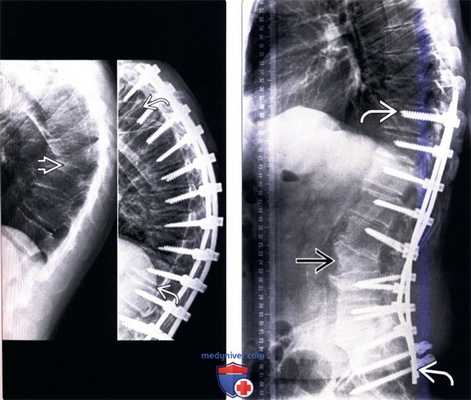

(Справа) Рентгенограммы позвоночника в прямой и боковой проекциях: случай протяженного спондилодеза грудного и поясничного (до уровня L5) отделов позвоночника. В большинстве случаев стабилизацию не рекомендуется заканчивать на уровне сегментов, смежных с сегментами с выраженными дегенеративными изменениями, особенно если здесь имеет место фиксированный наклон или подвывих позвонка. Проксимальный сегмент конструкции не должен оканчиваться ниже проксимальной структуральной грудной дуги искривления. Окончание протяженной конструкции на уровне L5 может привести в дальнейшем к выраженной дегенерации диска L5-S1. Поперечные коннекторы используются в первую очередь для придания конструкции ротационной стабильности.

(Слева) Рентгенограмма в боковой проекции: выраженная кифотическая деформация грудного отдела позвоночника. Согласно данным исследований, тяжесть клинической симптоматики возрастает пропорционально прогрессированию сагиттального дисбаланса. Кифотическая установка является более благоприятной для верхнегрудного отдела, однако плохо переносится пациентами при поясничной локализации. После задней транспедикулярной стабилизации позвоночника отмечается некоторое уменьшение выраженности кифоза.

(Справа) Рентгенограмма в боковой проекции: случай заднего спондилодеза грудопоясничного отдела позвоночника с продолжением до крестца и педикулярной субтракционной спондилотомии L3, выполненных с целью восстановления поясничного лордоза. Поскольку сколиоз — это деформация позвоночника во всех трех плоскостях, а также то, что нередко он у взрослых сопровождается дегенерацией межпозвонковых дисков, сколиоз поясничного отдела позвоночника нередко приводит к выраженному сглаживанию нормального поясничного лордоза и даже формированию здесь кифотической деформации, что приводит к развитию положительного сагиттального дисбаланса.